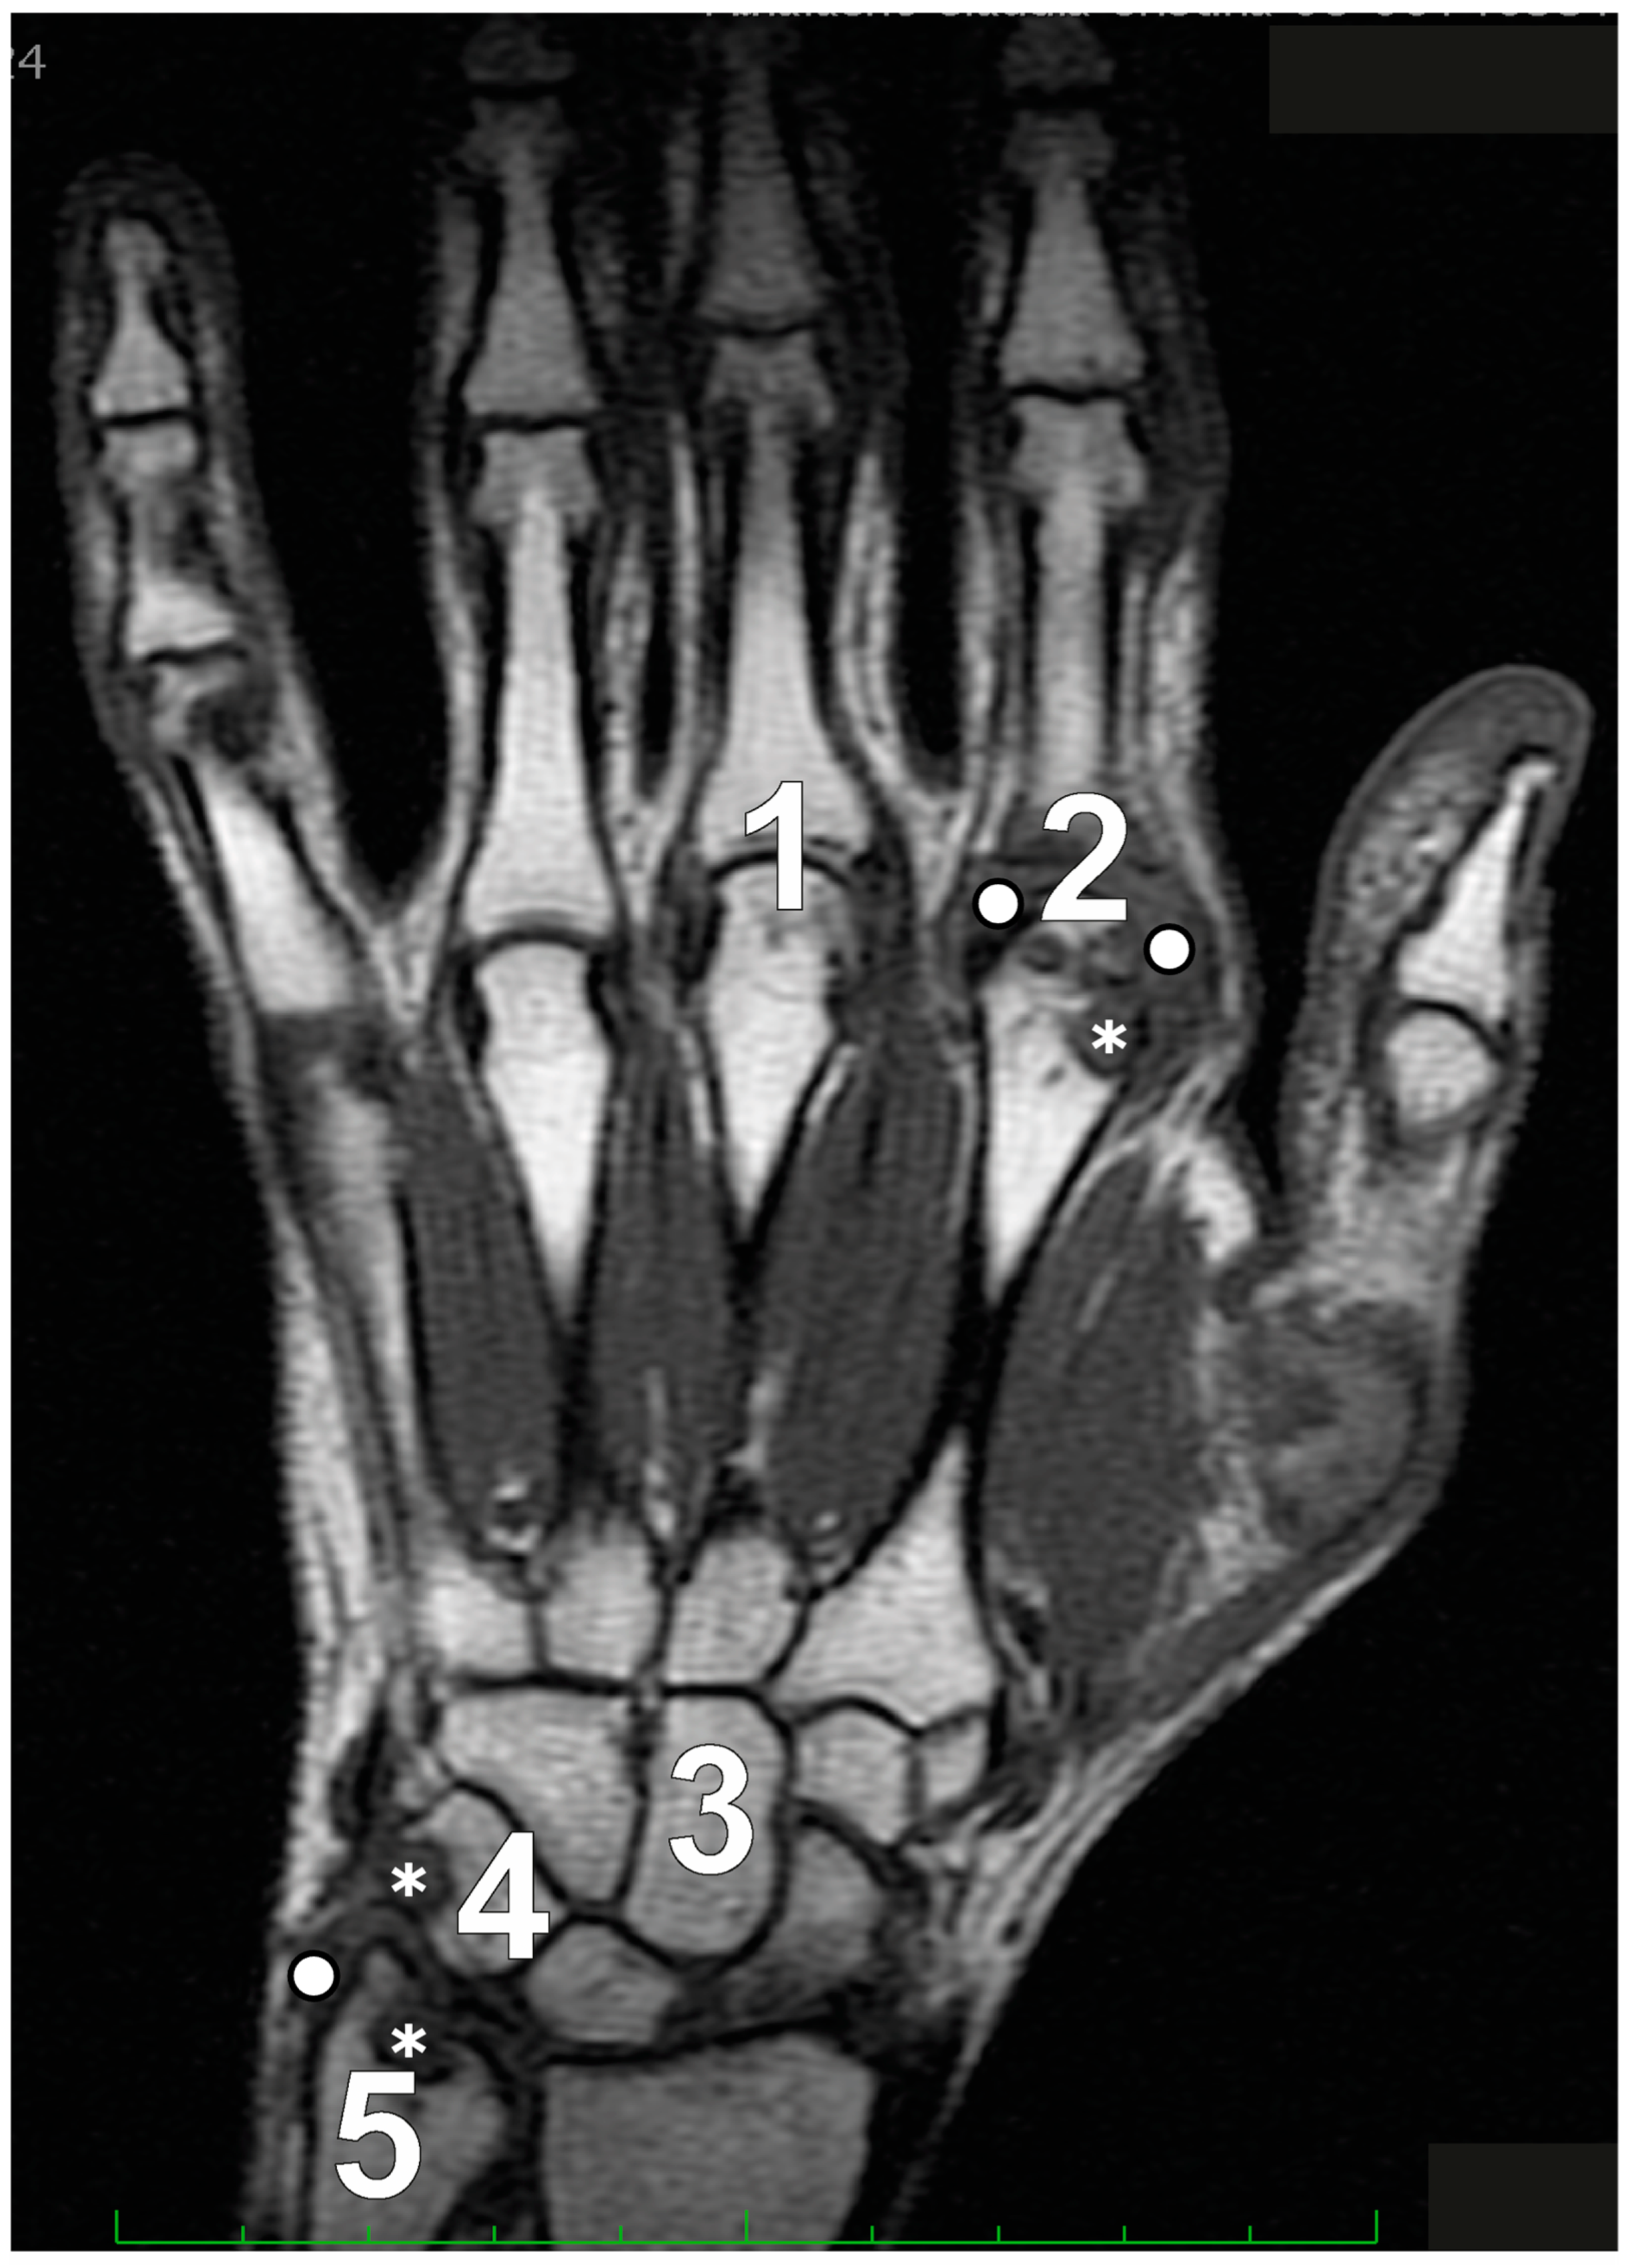

| Synovitis | Soft tissue, characterized by increased thickness or volume, visible on T1-weighted images, and with an elevated water content—which appears as a high signal on fat-suppressed T2-weighted images—is assessed for inflammation. Three regions of the wrist are evaluated: the radio-carpal, the intercarpal–metacarpal, and the distal radio-ulnar joints of either the dominant wrist or the most inflamed wrist. For the hand, an evaluation is conducted on the MCP joints 2–5 of either the dominant side or the side that is most inflamed. This evaluation can be performed with or without gadolinium enhancement, which shows a signal intensity increase at 4–5 min post-injection. | 0 (normal) to 3 (mild, moderate, severe) for each region/joint; maximum: 21 |

| Osteitis | Recognized within the subchondral trabecular bone, this lesion presents with poorly defined margins and characteristics of a signal suggestive of increased water content, which may also appear in association with erosion. The lesion appears as a high signal on fat-suppressed T2-weighted and STIR MRI images and as a low signal on T1-weighted images. Each bone in either the dominant or the most inflamed hand–wrist is scored separately to assess these features. | 0 (normal), (1) 1–33% of bone, (2) 34–66% of bone, and (3) 67–100% of bone showing increased water content. Maximum: 69 (45 for wrist alone) |

| Erosions | Sharply defined bone lesions located adjacent to joints, visible in two different imaging planes, are characterized by a visible cortical break in at least one plane. These lesions exhibit a reduction in the normal low signal intensity typically seen in cortical bone on T1-weighted MRI scans, as well as a decrease in the high signal observed on T2-weighted scans. Similar to the evaluation method used for osteitis, each bone in the wrist and hand is individually assessed to identify and score these specific features. | 0–10, according to 10% increments of bone eroded. Maximum: 230 (150 for wrist alone) |

| Tenosynovitis | Tenosynovitis assessment covers six extensor tendon and three flexor tendon compartments, ranging from the radioulnar joint to the hook of the hamate (wrist). For the MCP joints, the evaluation of flexor tendons is conducted within a region that extends from 1 cm proximal to 1 cm distal to each joint. The scoring of tenosynovitis is determined by measuring the maximum width of the effusion and/or tenosynovial enhancement, with measurements taken perpendicular to the tendon’s orientation. | 0–3 scale: 0 indicating no presence; 1 representing a peritendinous effusion and/or postcontrast tenosynovial enhancement of less than 1.5 mm; 2 for effusion or enhancement that is equal to or greater than 1.5 mm but less than 3 mm; and 3 for effusion or enhancement that is 3 mm or greater |